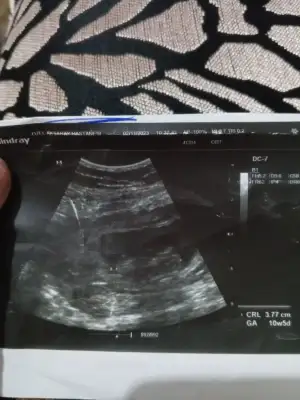

Kizlar bende 16 hafta 6 günlük hamileyim doktor dün kız dedi 100/de 95 dedi. İperleyen haflalarda cinsiyet değişikliği olqn varmı sizce benimkiside degisirmi benim durumumda olan varmı. Allah rızası için banada cevap yazarmisiniz benim GB opan varmı

Sevde49 gönderdim bu resim geçen ayın... Dünkü doktor kontrolü ntrolunde çekilen resimleride attım bakarmisiniz sayfamda Allah rızası için